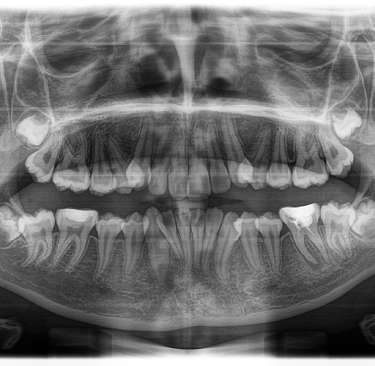

- Radiographies panoramiques : Ce type de radiographie offre une vue complète de votre bouche, y compris vos dents, votre mâchoire supérieure et inférieure, vos sinus et vos articulations temporo-mandibulaires. Elles sont généralement utilisées pour planifier des traitements orthodontiques ou des interventions chirurgicales, ou pour évaluer l'état de la mâchoire et des dents de sagesse.